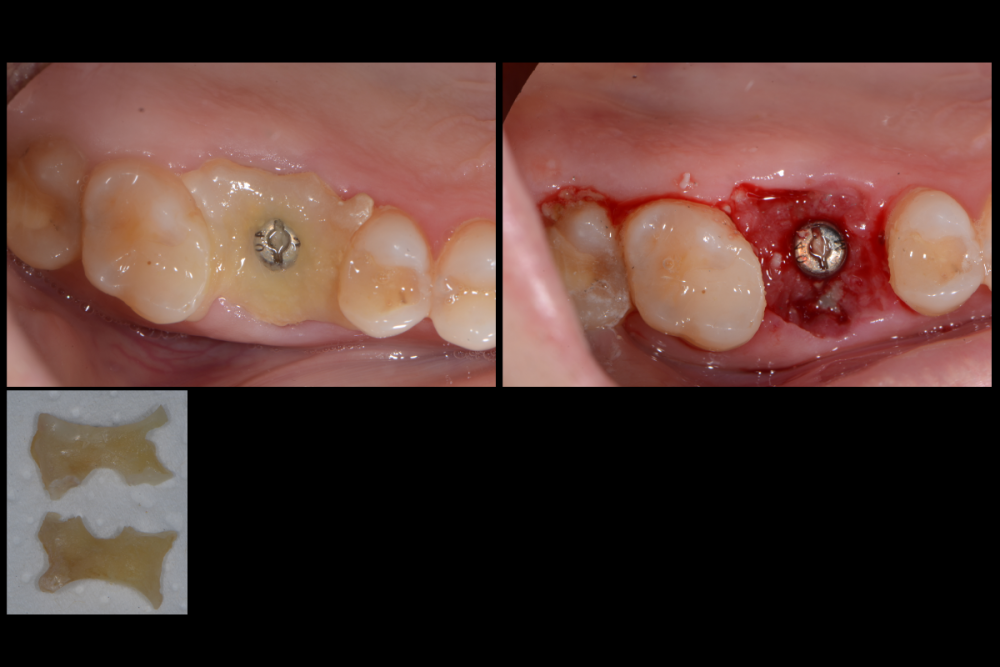

Карен Аванесов Опубликовано 10 ноября, 2021 Автор Поделиться Опубликовано 10 ноября, 2021 Придерживаясь правил форума, второе сообщение содержащее фотоматериал выдержанно в лучших традициях русской словестности, без сквернословия и непонятных иностранных слов, без применения шовного материала, широких формирователей десневой манжеты, без мягкотканной и прочей аугментации (наращивание костей что то все же не звучит прилично)), а самое главное, время затраченное на всю операцию 60 минут (имплантаты на нижней челюсти установил по лазерной технологии, без разрезов, Лазер - сила!). Время ожидания до ортопедического этапа 3 месяца. 6 1 Ссылка на комментарий

Марья Моревна Опубликовано 13 ноября, 2021 Поделиться Опубликовано 13 ноября, 2021 А что это такое кругленькое виднеется в лунке небного корня на самом левом из трех снимков над панорамой? 1 Ссылка на комментарий

Карен Аванесов Опубликовано 14 ноября, 2021 Автор Поделиться Опубликовано 14 ноября, 2021 13.11.2021 в 08:55, annda сказал: У инженера гиперболоид был, однако Не претендую на раскрытие секретов, видимо, что- то сакральное. Анна Анатольевна, в данном контексте, упоминание лазера, не более чем гипербола. Улыбайтесь чаще, Вам идет улыбка) 13.11.2021 в 20:19, Марья Моревна сказал: А что это такое кругленькое виднеется в лунке небного корня на самом левом из трех снимков над панорамой? А Вы Марья Моревна глазастенькая! Это воздушный пузырь, там две перфорации синуса, после удаления кисты. Ссылка на комментарий

Карен Аванесов Опубликовано 14 ноября, 2021 Автор Поделиться Опубликовано 14 ноября, 2021 (изменено) 13.11.2021 в 20:19, Марья Моревна сказал: А что это такое кругленькое виднеется в лунке небного корня на самом левом из трех снимков над панорамой? Это некий цимус-изюминка, в этой работе Изменено 14 ноября, 2021 пользователем Карен Аванесов Ссылка на комментарий